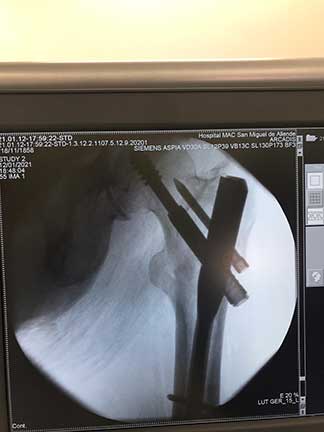

Fractura

de cadera

Es la pérdida de la continuidad del tejido óseo en la articulación de la cadera, producidas por caídas o traumatismos de alta energía, la cual se caracteriza por dolor intenso, incapacidad funcional, chasquidos, acortamiento y rotación de la pierna, el diagnóstico definitivo es por radiografía o tomografía.

¿Por qué se realiza?

El tratamiento en pacientes adultos regularmente es quirúrgico, el cual se realiza con implantes de metal que recuperan la anatomía normal de la articulación similar a la previa fractura, los cuales pueden ser clavos, placas, tornillos o prótesis.

Cuidados después de la intervención

La intención de un tratamiento de fractura siempre es movilizar al paciente lo más pronto posible, los tiempos para movilizar al paciente puede ser desde el primer día del tratamiento hasta algunas semanas dependiendo del tipo de fractura, tipo de paciente y el implante utilizado.

Resultados esperados

El objetivo es recuperar la función previo a la fractura con la misma fuerza, movimiento y estabilidad, esto se puede lograr si se realiza un diagnóstico adecuado y un tratamiento con una buena planeación.